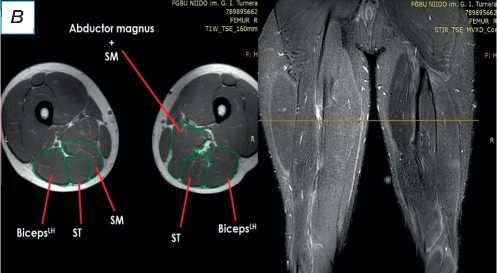

При поступлении в центр пациенту выполнены лучевые методы исследования нижних конечностей, в частности панорамная рентгенография и компьютерная томография (КТ) нижних конечностей; сравнительная МРТ мягких тканей правого и левого бедра (рис. 2). По данным рентгенографии и КТ-исследования, костно-суставной патологии не обнаружено. По результатам МРТ определены повреждения всех трёх мышц различной степени тяжести — SM, ST, BicepsLH (расположены в порядке убывания; см. рис. 2, а ). Длинная головка двуглавой и полусухожильная мышцы, вероятно, были оторваны у места крепления и не подверглись значительной ретракции; начало брюшка полуперепон-чатой мышцы визуализировано на границе верхней и средней трети бедра (ретракция 9 см).

Рис. 2. Сравнительная магнитно-резонансная томография мягких тканей правого и левого бедра (аксиальные и фронтальные срезы): а — изменение нормальной архитектоники полусухожильной, полуперепончатой и длинной головки двуглавой мышцы на уровне верхней трети правого бедра; б — на данном уровне не прослеживается мышечное брюшко полуперепончатой мышцы; в — на границе верхней и средней трети прослеживается мышечное брюшко полуперепончатой мышцы, спаянное с большой приводящей; определяется разница по форме и диаметру поперечника полусухожильной мышцы; г — на уровне средней трети отчётливо проявляются мышечное брюшко полусухожильной мышцы, несоответствие поперечного диаметра полуперепончатой и полусухожильной мышц с контралатеральной стороной, гипертрофия короткой и длинной головки бицепса; д — аналогичная картина и на границе средней и нижней трети. ST ( m. semitendinosus ) — полусухожильная мышца; SM ( m. semimembranosus ) — полуперепончатая мышца; BicepsLH ( m. biceps femoris ) — длинная головка двуглавой мышцы.